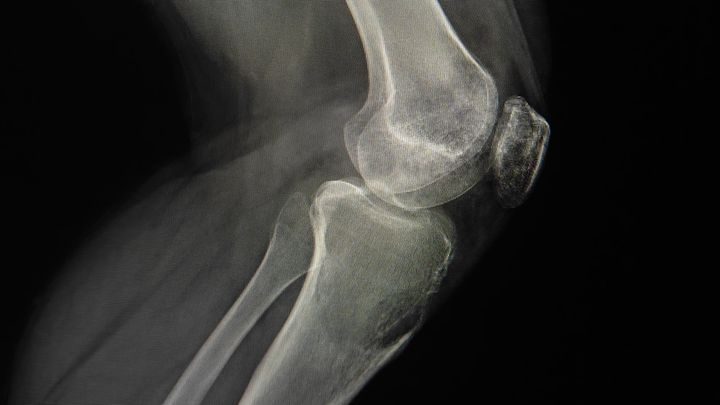

Estoy recaudando fondos para mi novio, quien actualmente tiene un tumor agresivo en la rodilla (tibia). En este momento estamos en espera de los resultados de su biopsia para conocer exactamente el diagnóstico y el tratamiento que seguirá.